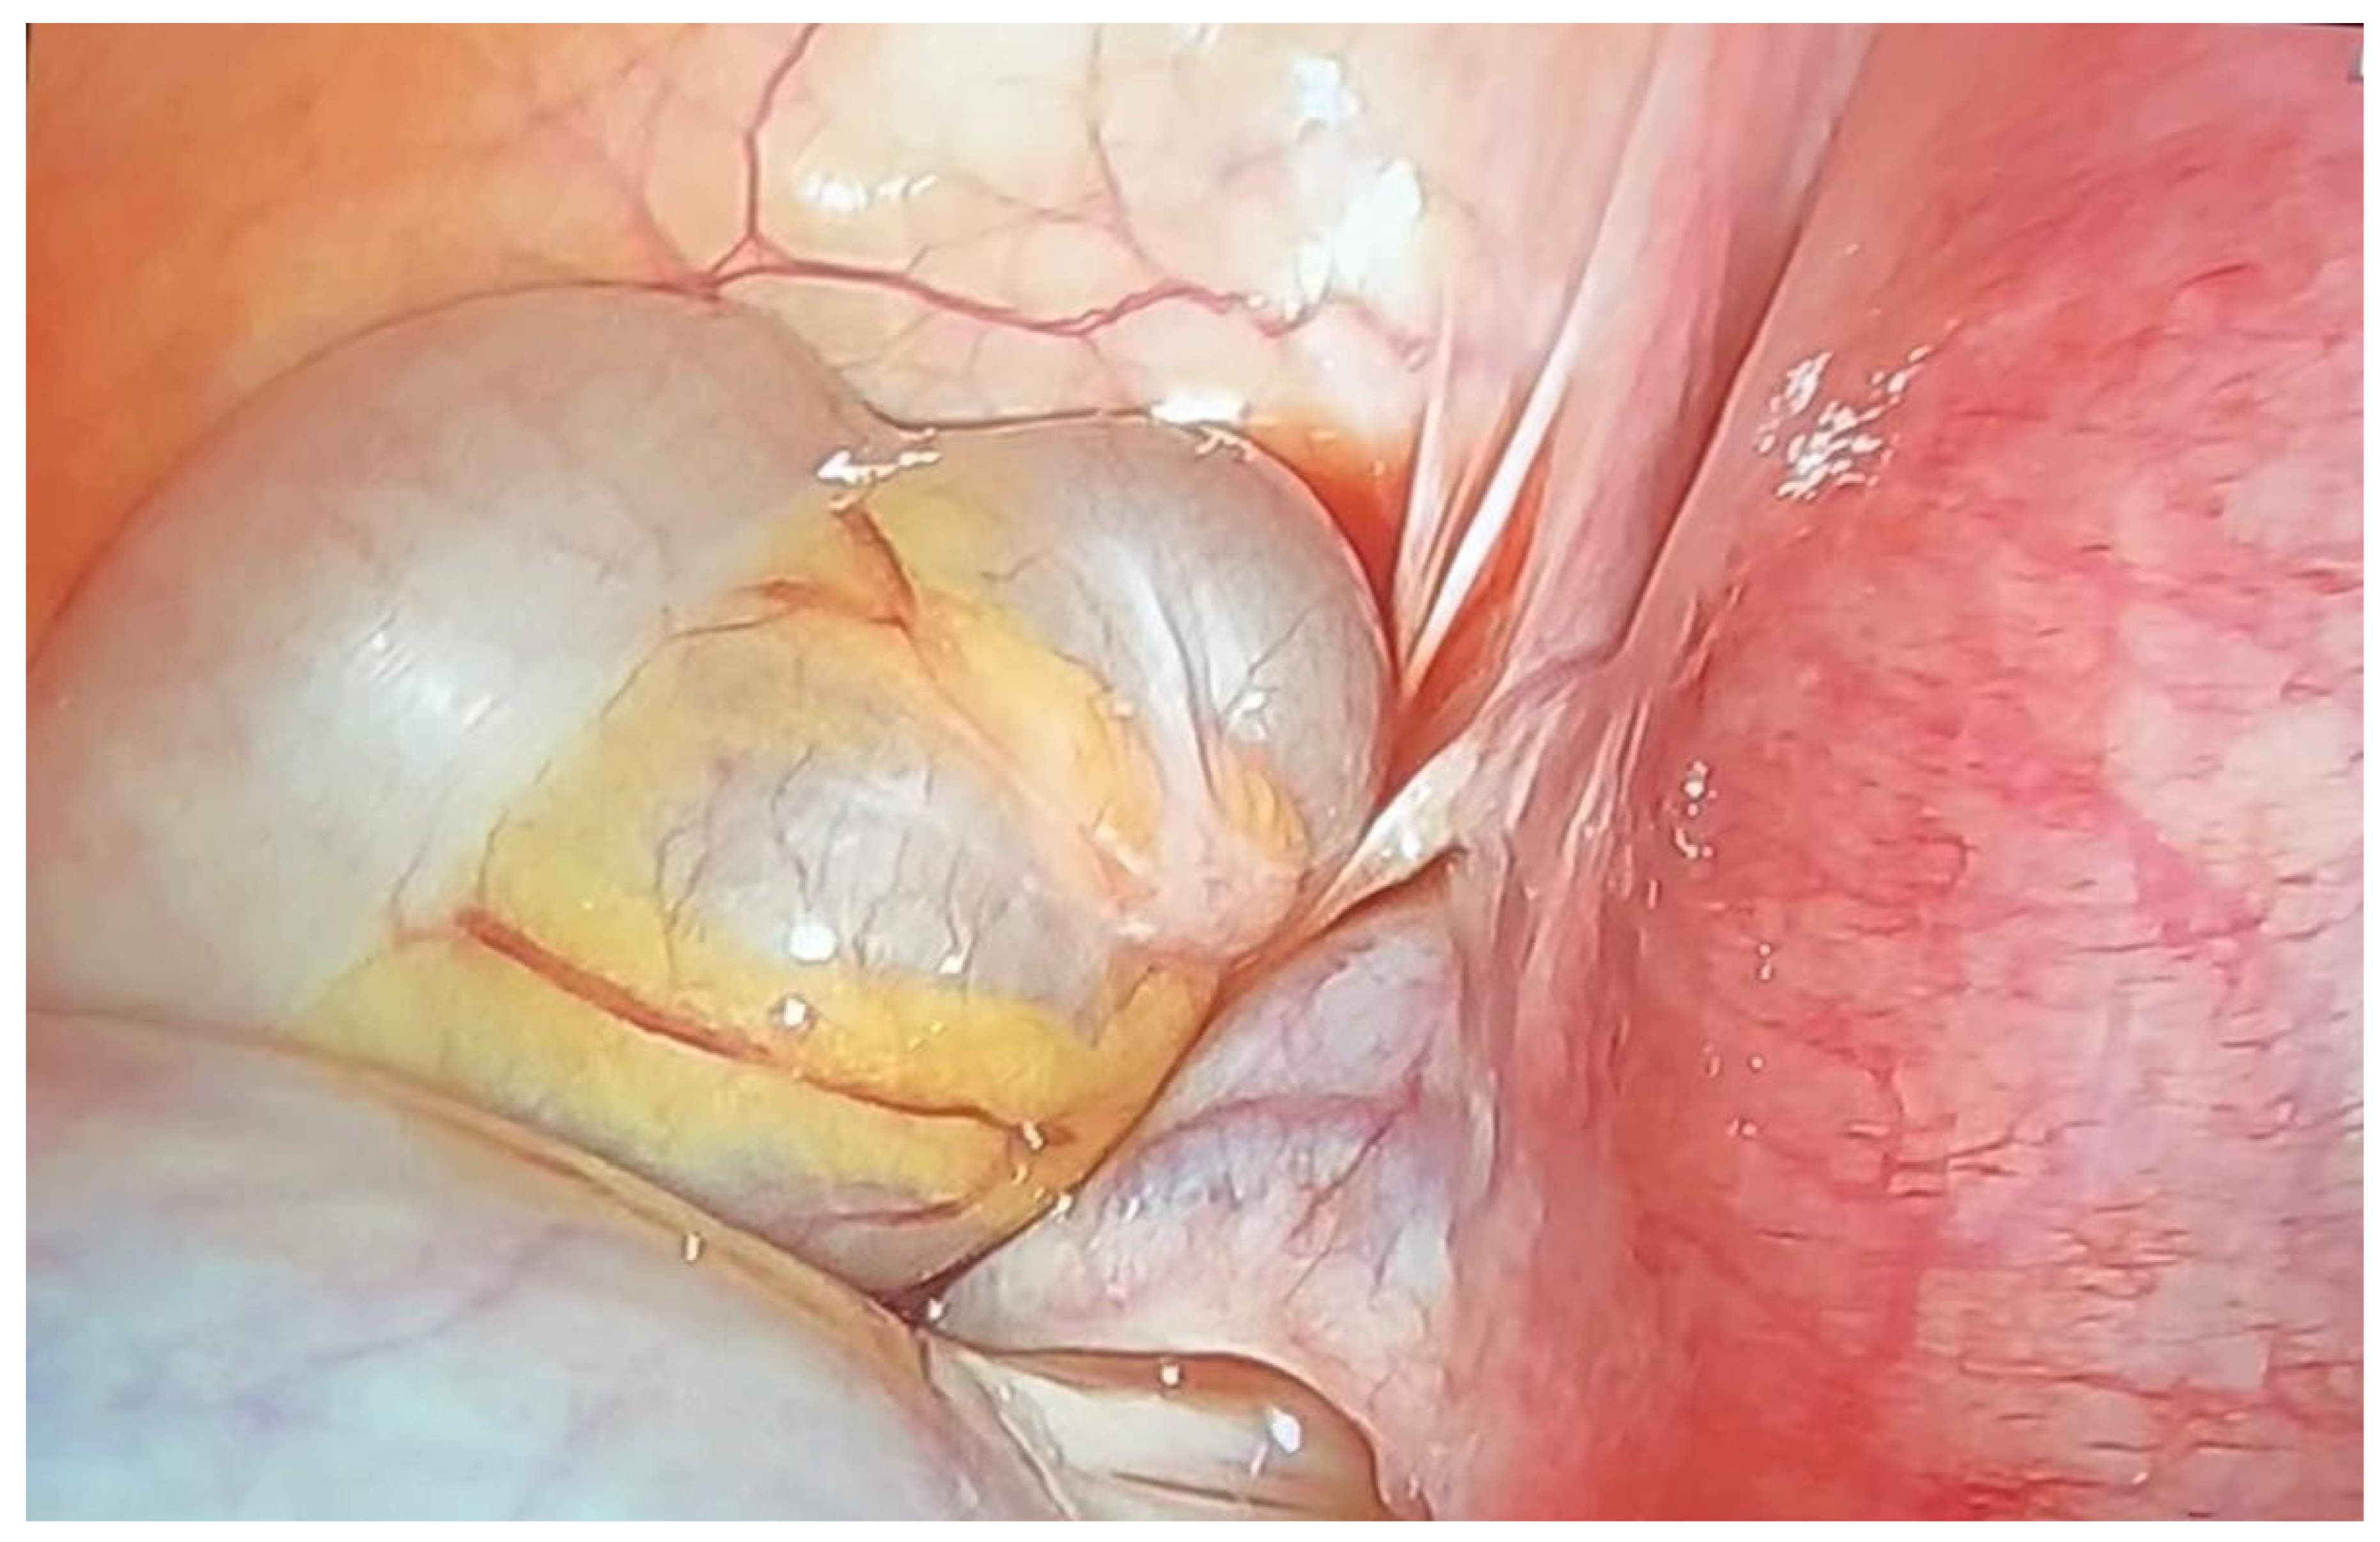

Nevertheless, the patient reattended the emergency room at week 19, presenting with acute onset of left lower quadrant pain. In this case, the ultrasound examination showed a positive whirlpool sign and on suspicion of ovarian torsion, the patient underwent an emergency diagnostic laparoscopy. Intraoperative findings revealed a 12 cm mass and twisting of two turns at the left infundibulopelvic ligament (Figure 3).

Figure 3. Detail of adnexal tumor formation with torsion.